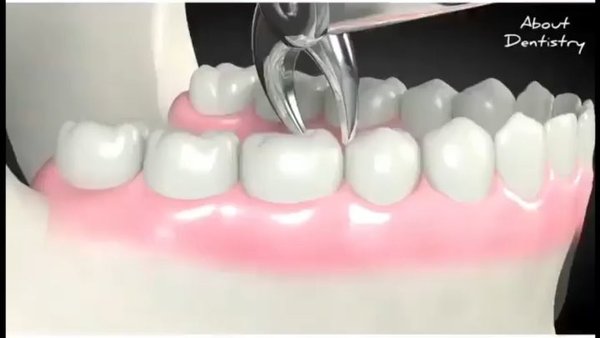

Все проще, чем кажется . Поэтапно: ️Удаляем твердые зубные отложения с зубов (камни) = получаем здоровые дёсны, пародонт и все его составляющие ⏩ отсутствие рецессий десны, оголения корней, подвижности зубов ️Убираем пигментированный налет с зубов (от употребления чая, кофе, других красящих продуктов) = здоровая эмаль и все подлежащие ткани ⏩ отсутствие кариеса и его осложнений (а их немало) ️Полируем и насыщаем средствами для защиты от кариеса = что говорит само за себя . И все это по цене одного кариеса! . Проще и выгоднее, чем по… — Читать дальше

том пожинать плоды многолетних бойкотирований посещения кабинета стоматолога . Работа врача Азадова Аскерхана По всем интересующим вопросам жду в директ Или ватс ап в шапке профиля.